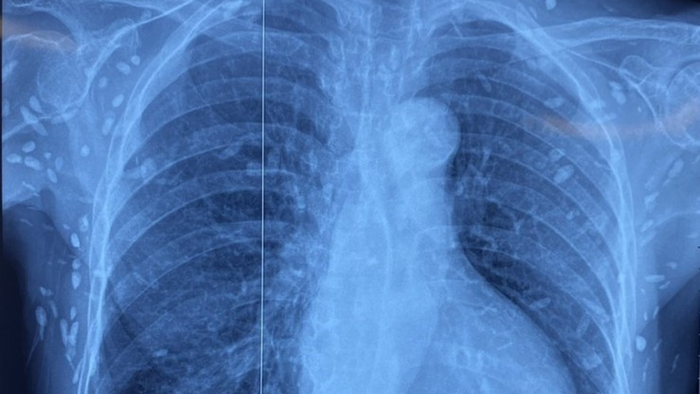

Bệnh nhân được chuyển lên từ tuyến dưới trong tình trạng rối loạn ý thức, đe dọa suy hô hấp. Kết quả chụp cắt lớp vi tính sọ não và X-quang ngực cho thấy nhiều nốt cản quang rải rác trong nhu mô não và dưới da vùng ngực - bụng. Một số u cục có thể sờ thấy dưới da vùng ngực và cánh tay.

Mặc dù xét nghiệm kháng thể IgM với sán dây lợn âm tính, song các hình ảnh tổn thương trên phim X-quang gợi ý bệnh nhân từng nhiễm ấu trùng sán dây lợn, các nang sán đã vôi hóa và tồn tại lâu dài trong cơ thể. Sau quá trình điều trị theo phác đồ, tình trạng người bệnh ổn định, được cho ra viện và tiếp tục theo dõi tại tuyến dưới.

Nhiều nốt cản quang dưới da thành ngực-bụng và chi trên của bệnh nhân

Người có thể bị nhiễm bệnh khi ăn thịt lợn gạo chưa nấu chín hoặc rau sống dính trứng sán. Đặc biệt, khi ấu trùng sán xâm nhập vào não hoặc mắt, bệnh nhân có thể gặp các biến chứng nghiêm trọng như động kinh, rối loạn tâm thần - vận động, đau đầu, giảm thị lực... Một số nang sán có thể tự thoái hóa hoặc bị vôi hóa, tạo nên hình ảnh cản quang rõ nét trên phim X-quang - như trong trường hợp bệnh nhân nói trên.